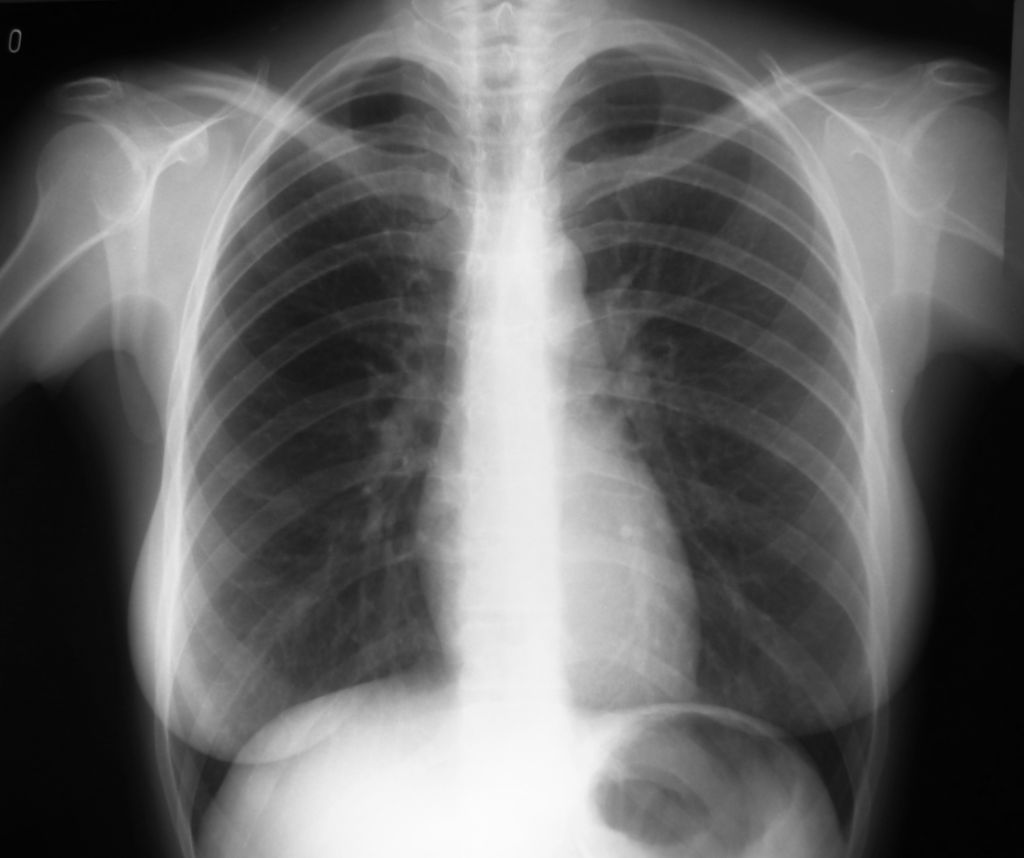

Anteriormente cité las sustancias irritantes dentro de la composición química del tabaco. Estas sustancias pueden causar algunas consecuencias respiratorias como la EPOC (enfermedad pulmonar obstructiva crónica). Eso es bronquitis crónica y efisema pulmonar.

Además, incrementan la producción de moco que es difícil de expulsar, pudiendo causar tos típica del fumador o dificultad respiratoria. Esto se debe a la parálisis de las células ciliadas producidas por el tabaco. Ellas se encargan de movilizar el moco y las partículas pequeñas que entran en los pulmones, pero con ellas paralizadas no pueden…

En definitiva, el fumador notará:

- Tos crónica irritativa

- Expectoración

- Disminución de la capacidad pulmonar (temporal o irreversible)

- Mayor propensión a infecciones respiratorias y otorrinolaringólogas.